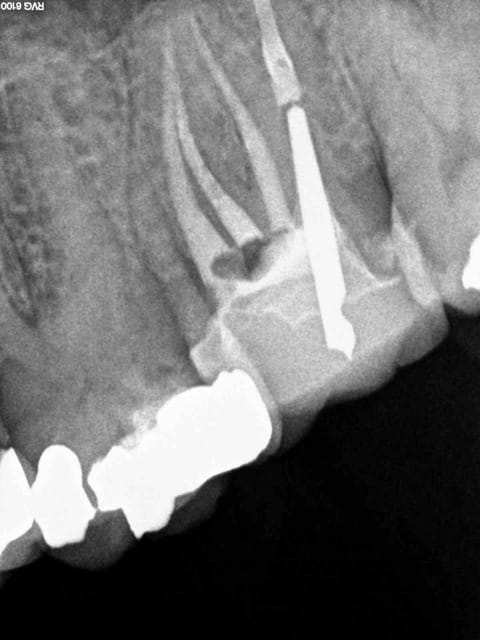

Voici toutes les radios du début à la fin :

On touche au but après 2H 30 de dépose-retraitement. Mv2 en Y heureusement pour moi. Obturation gutta chaude le tout pour 2 balles.

Le mystère reste entier concernant le canal palatin, la gutta ayant disparue probablement lors de la réalisation du tenon.

Le réchauffement de la pèche palatine a eu lieu 8 ans après.